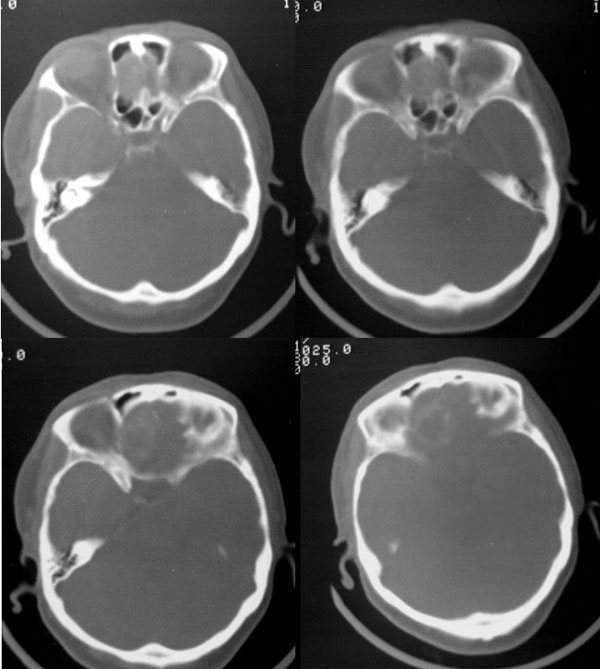

平扫前颅底区类圆形骨样高密度影,中心可见低密度影,病变向上生长突入额叶,向下生长突入筛窦,说明病灶来源于额骨水平部,脑膜瘤只能引起颅底骨质的增厚,突入筛窦的几率不大.所以我认为应该首先考虑前颅底骨软骨瘤可能大.如果病变不是来源于颅底骨质,首先应该考虑颅咽管瘤或脑膜瘤.

大家看四张骨窗片:病灶最大截面在筛窦,并以此为中心向上侵入额叶,向两侧侵入双眼眶,双眼眶内侧壁亦见骨质吸收破坏,依此可确立病变位于脑外。在此部位符合上述特点的肿瘤,能想到的有骨软骨瘤或脑膜瘤,从常见病考虑,以脑膜瘤可能性大。

前颅窝底钙化性脑外肿块,右侧前床突轻度硬化,按发病部位来讲,最支持脑膜瘤。

颅咽管瘤位置太靠前且本例中央区更象软组织密度;骨软骨瘤多发生于鞍区且密度多不会如此混杂;海绵状血管瘤钙化形态多呈散发少呈如此规则环状强化,且多发于鞍区硬膜外;筛窦源性肿瘤主体应位于窦腔,窦腔骨质多有改变如嗅母;明显脑外特征则不支持脑内肿瘤如胶质瘤了。